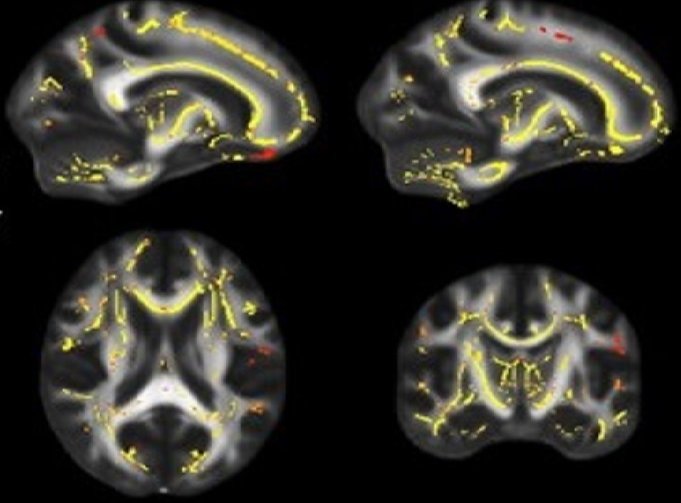

Le scansioni cerebrali mostrano pixel gialli e rossastri che rappresentano le aree in cui la funzionalità della sostanza bianca è associata a livelli più elevati di forma fisica. Le immagini si basano su dati cumulativi ottenuti da pazienti in uno studio che mostra potenziali legami tra idoneità fisica e deterioramento della sostanza bianca.

Lo studio, pubblicato sul Journal of Alzheimer's Disease, si è concentrato su un tipo di tessuto cerebrale chiamato «sostanza bianca», che è composto da milioni di fasci di fibre nervose usate dai neuroni per comunicare attraverso il cervello.

A differenza degli studi precedenti che chiedevano ai partecipanti di auto-valutare la propria forma fisica, la nuova ricerca ha misurato obiettivamente la forma cardiorespiratoria con una formula scientifica chiamata «assorbimento massimale di ossigeno». Gli scienziati hanno anche usato scansioni cerebrali per misurare la funzionalità della sostanza bianca di ogni paziente.